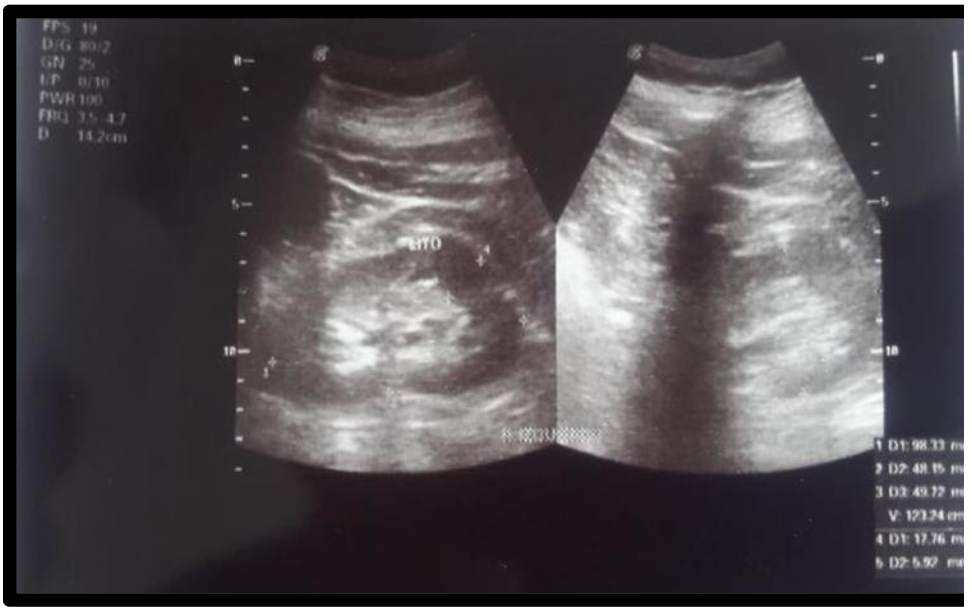

Renal lithiasis in a patient with primary hypothyroidism

Case report.

Santiago Silva (Author)

64-73